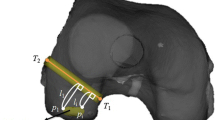

To create the femoral tunnel, a 3D lateral image of distal femur sagittal view was shown on the navigation computer monitor. The femoral footprints of the AM bundle were marked using the navigation awl with the assistance of the computer monitor images projected during preoperative planning. Transtibial drilling through each tibial tunnel was our first option. However, if the femoral marking holes were hard to reach using the transtibial approach, we created femoral tunnels through the accessory anteromedial portal. When we selected the anterior medial portal approach, simulation was done before inserting the guide wire. On the navigation computer screen, the 3D image of the distal femur was rotated to face the posterolateral aspect of the femur. The virtual femoral tunnel diameter was set to the real diameter of the AM graft. The navigation pointer tip was placed at a small hole on the AM footprint, and knee was flexed 90 to 120–130 degrees. When flexing the knee, risk of the posterior wall breakage and sufficiency of the bone tunnel length were evaluated (Fig. 4).

Diameter of the virtual femoral tunnel is set at the actual graft diameter, and a small hole made by awl is pointed by the passive navigation pointer. Using the trace, risk of lateral femoral condyle injury and posterior wall breakage, and bone tunnel length are evaluated. a Knee joint bent 90 degrees: virtual femoral tunnel revealed risk of femoral condyle injury and insufficient bone tunnel length. b Knee joint bent 120 degree: risk of femoral condyle injury was avoided by bending the knee joint, and sufficient bone tunnel length was secured